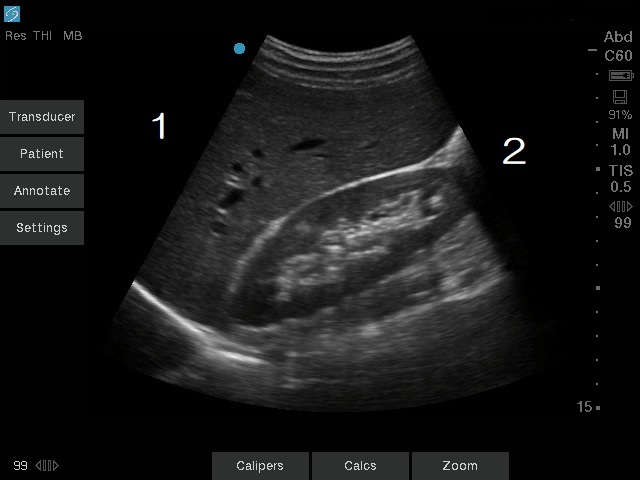

Coronal Transducer Orientation Liver and Right Kidney Image

1. Toward Patient's Head

2. Toward Patient's Feet